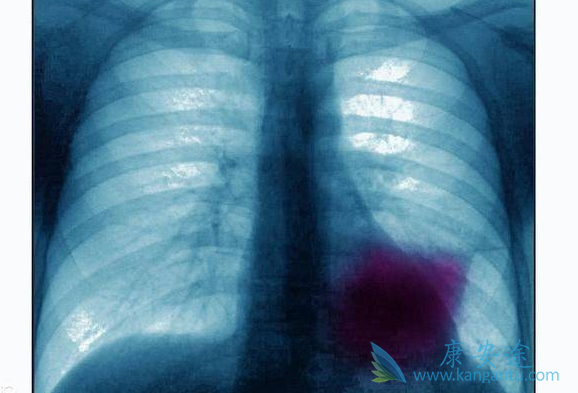

当人体的免疫系统出现问题,无法彻底清除癌细胞时,肿瘤就会产生。其次,肺部作为人体五脏之华表,一旦发生癌变则会影响整个人体的新陈代谢,而且肺癌极其容易发生转移。肺癌晚期患者手术的风险极高,而且复发的可能性也极大。所以现在医学界普遍对肺癌进行保守治疗,对肿瘤进行控制,防止其转移扩张。只要肿瘤的活性能够被压制,可以保持相对静止状态,并且能够通过药物减少患者的生理痛苦,即使肿瘤无法清除,也不会危及患者生命,这就是医学界提倡的“带瘤生存”。

目前医学界提倡对于肺癌,尤其是晚期肺癌的治疗采取保守疗法,比如肺癌生物治疗,是目前医学界比较提倡的一种癌症治疗的新型方案。相较于手术、化疗、放疗三大常规疗法的高风险性,生物免疫疗法(DC-CIK)对于肺癌的治疗更为有效。生物免疫疗法又叫自体细胞免疫治疗技术,其原理是通过提取患者自身的免疫细胞,通过体外抗癌活性化培育后大量回注患体。这种疗法的最大优势是利用患者自身的细胞对癌细胞进行抑制和杀灭,不会产生任何生物排斥性,并且能够提高患者自身的免疫力,对肺癌的扩散和转移都有较好的抑制作用。